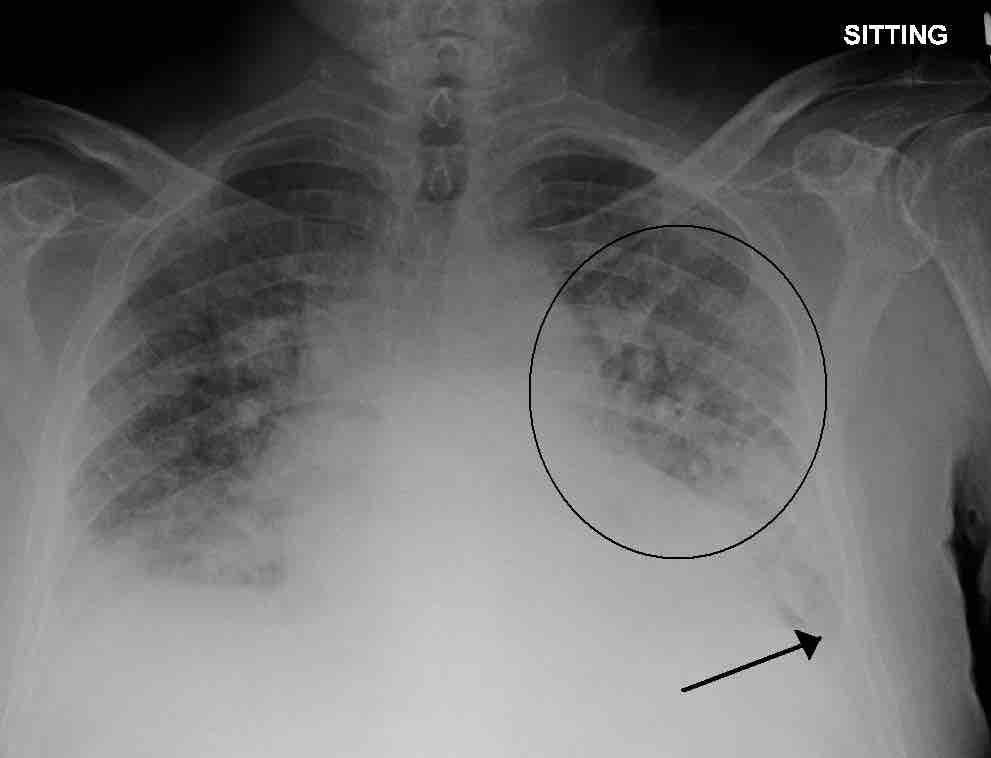

A physiological shunt can develop if there is infection or edema in the lung which decreases ventilation, but does not affect perfusion; thus, the ventilation/perfusion ratio is affected. Pulmonary edema with small pleural effusions on both sides (as shown) can cause changes in the V/Q ratio.